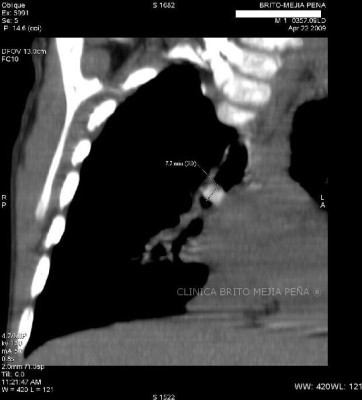

Hernia morgagni coronal